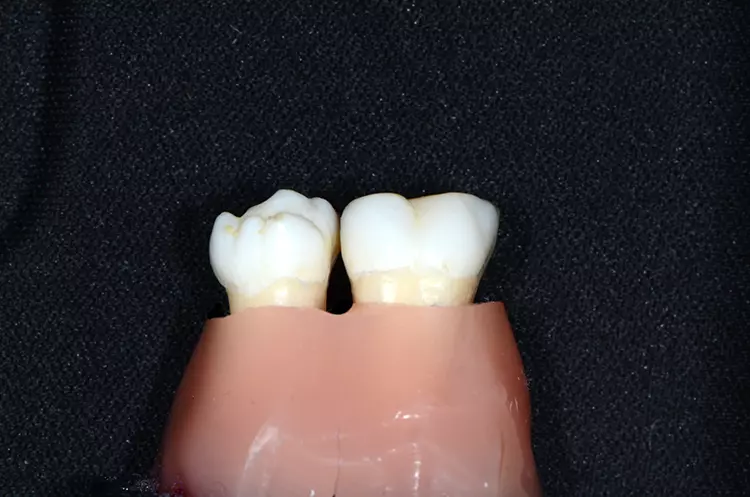

In der Praxis werden an Patienten zuweilen mit Messsonden diverse Größen ausprobiert, um eine entsprechende Empfehlung abzugeben [26]. Allerdings ist ihr Wert umstritten. Eine korrekt angepasste Interdentalraumbürste sollte den kompletten Interdentalraum reinigen und mit „mittlerem“ Druck ein- und auszuführen sein. Wenn sie zu dünn ist, hat sie eine zu geringe Reinigungswirkung; ist sie hingegen zu dick, besteht Traumatisierungsgefahr. Abbildung 2 zeigt die Einprobe und Auswahl am Beispiel des Interdentalraums 41/42.